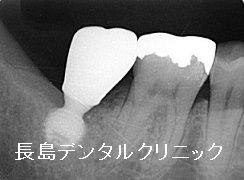

左下一番奥歯(7番目の歯)が

歯周病で欠損したため

歯茎が治癒するまで

2~3か月待ってから

インプラントを行おうとしたところ

骨がなく他院から紹介された患者様です。

下顎の一番奥歯(7番目の歯)は

神経までの距離が元々

少ない場合があります。

そのために歯周病になると

周りの骨が吸収し

抜歯を行い

歯茎が治癒する数か月

さらに吸収が進みますので

インプラントを埋入しようとすると

神経までの骨の厚みが足りず

インプラントが埋入できないということになります。